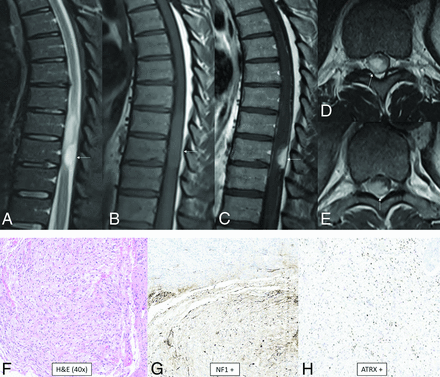

High-grade astrocytoma with piloid features is a circumscribed astrocytic glioma that has not yet been assigned a WHO grade but behaves like WHO grade 3 or 4.8,15 A hallmark of this tumor is its unique methylation profile.32 The most common genetic abnormalities are cdkn2A/B deletion, MAPK pathway alteration (affecting NF1, BRAF, and FGFR1), and ATRX mutation or loss of expression. Histologically, tumors tend to show moderate cellularity, glioblastoma-like foci, moderate nuclear pleomorphism, a moderate mitotic rate, lack of necrosis, vascular hypertrophy, and infiltrative growth.32 Most occur in the posterior fossa (74%), usually in the cerebellum, followed by supratentorial then spinal locations. The median age is 41.5 years, with occurrence from pediatrics to the elderly and no sex predilection.32 There appears to be an association with neurofibromatosis type 1.33 Tumors tend to be T1-hypointense-to-isointense, T2-hyperintense, heterogeneously enhancing, non-diffusion-restricting, and non-necrotic with sharp or ill-defined margins (Fig 6).12

High-grade astrocytoma with piloid features. MR images demonstrate an eccentric T2-hyperintense mass (A) along the posterior thoracic cord with low T1 signal (B) and avid enhancement (C–E, arrows). Surrounding intramedullary T2-hyperintensity represents edema and/or tumor infiltration. Histology reveals an astrocytoma with piloid morphology (F), having NF1 (G) and ATRX (H) mutations in association with CDK2NA/B homozygous deletion. Whole-genome methylation profiling showed a match to high-grade astrocytoma with piloid features. Most of these tumors occur intracranially.